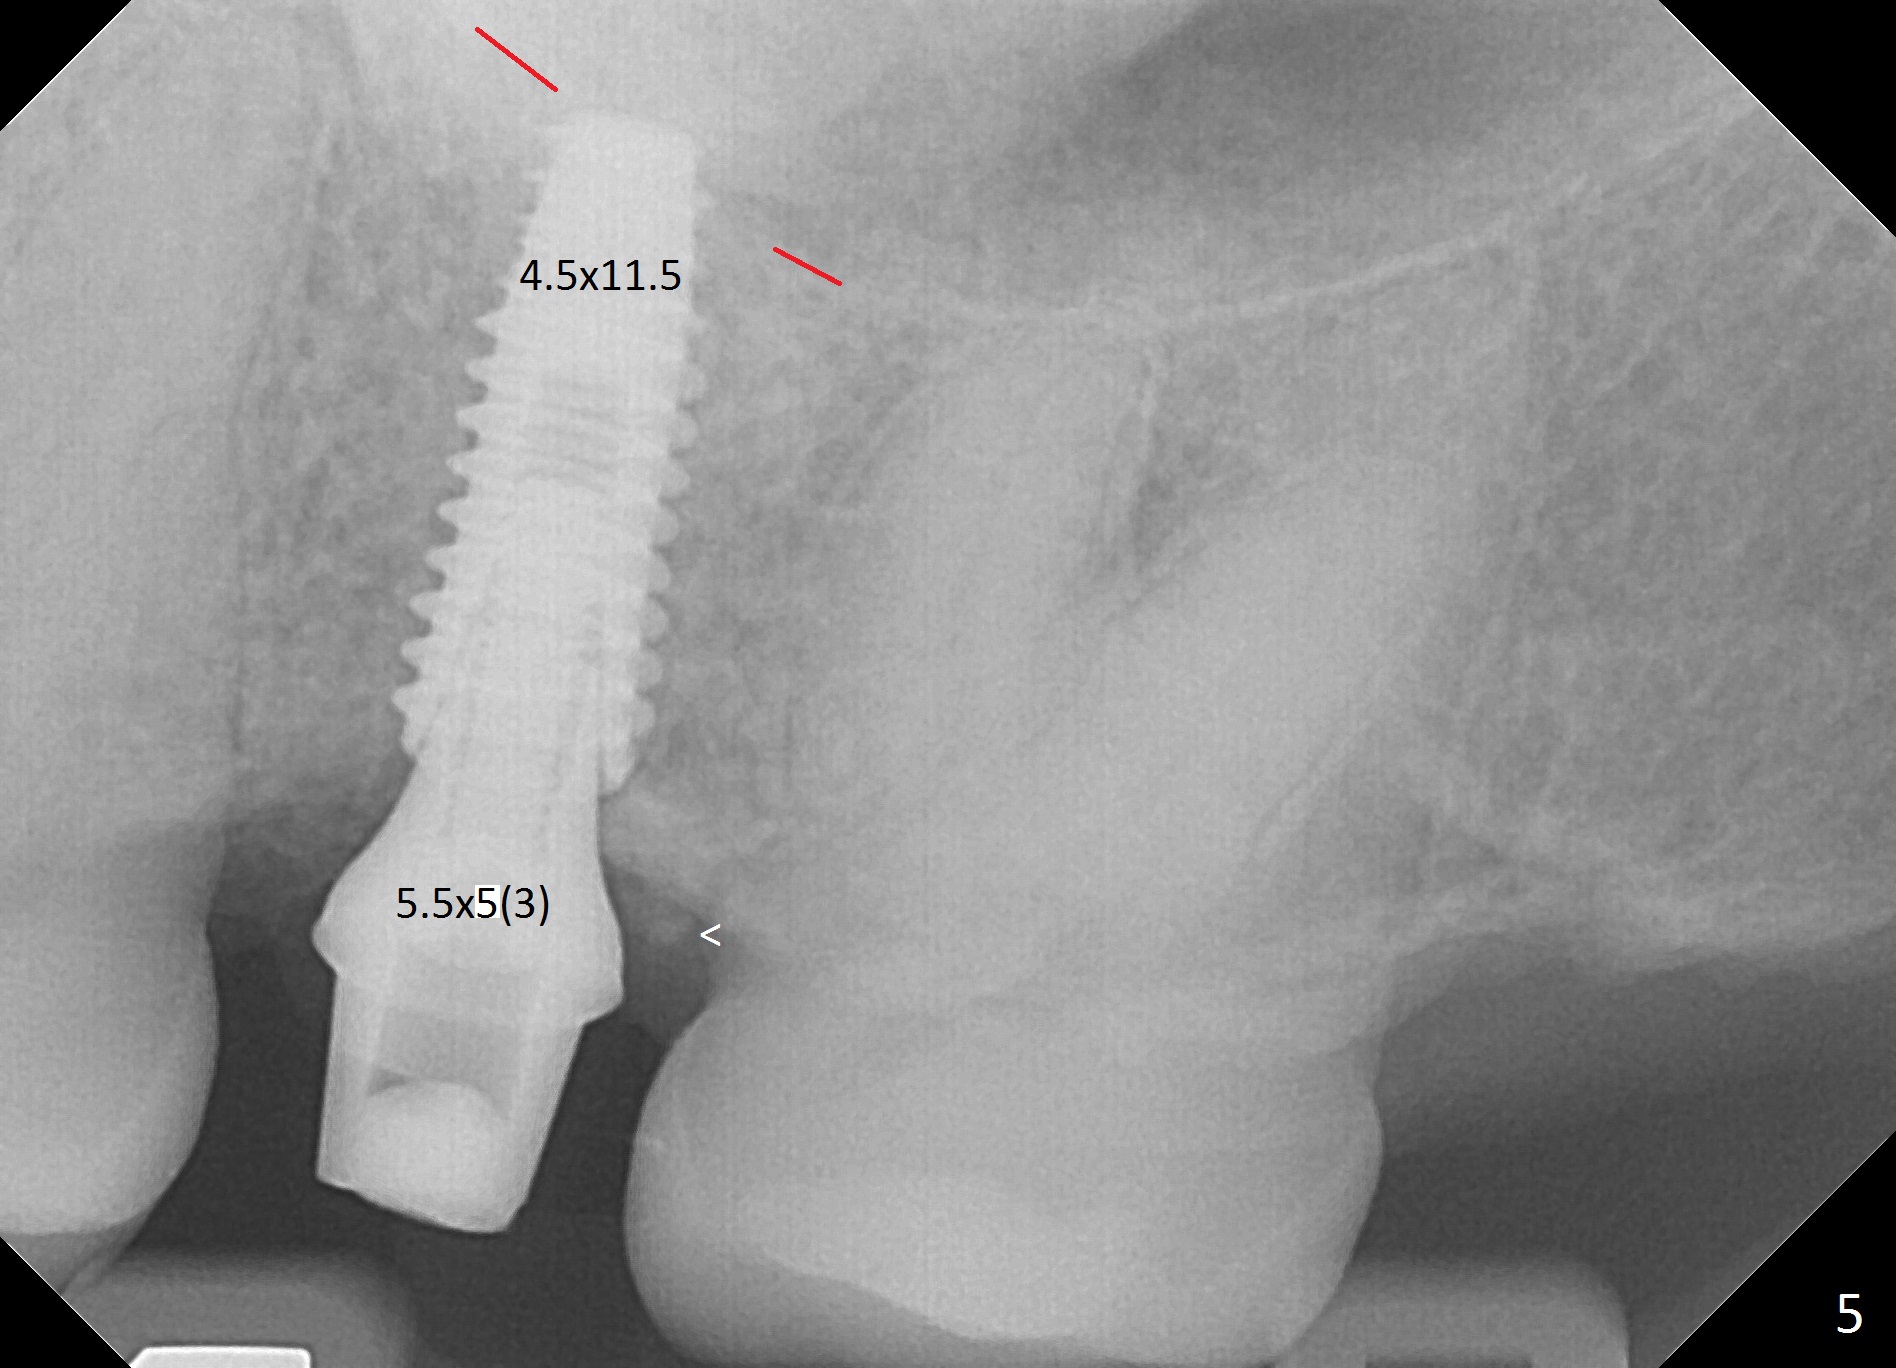

The edentulous area at #14 is moderately atrophic, After incision, the bone is too hard for #15 blade for bone expansion. Osteotomy is initiated with 1.2 mm drill, followed by insertion 1.3/2.3 mm bone expander (Fig.1). Use the same instruments are reused twice to change the trajectory (Fig.2,3). Finally Lindamann bur is utilized to move the osteotomy distally by ~ 2 mm; bone expansion continues until 2.4/3.7 mm expander for 13 mm with 50 Ncm (Fig.4). The last expander 3/4.4 mm barely enters the osteotomy for 6 mm. A 3.7 mm drill has to be used for 12 mm before placement of a 4.5x11.5 mm implant with >35 Ncm (Fig.5). A 5.5x5(3) mm abutment is placed with allograft (<) placed around the implant. Following suturing, periodontal dressing is applied around the implant. The abutment dislodges 3 months postop (Fig.6). Crown is delivered 3 weeks later. The abutment screw is retightened ~ 2 months later. He is a bruxer. The abutment screw is loose again <2 years post cementation (6 months post #18 screw retightenting and occlusal reduction), probably related to distal implant placement (Fig.7).